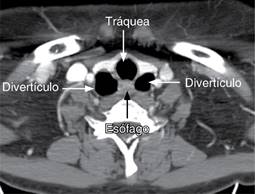

Figura 3: Tomografía a nivel cervicotorácico en corte axial, que muestra divertículos esofágicos anterolaterales.